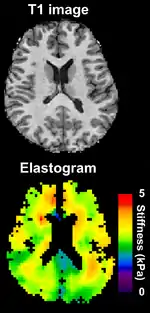

An anatomical MRI image of a brain (top) and an MRE elastogram of the same brain (bottom). The stiffness is in kPa of shear modulus.

Magnetic resonance elastography (MRE)[26] was introduced in the mid-1990s, and multiple clinical applications have been investigated. In MRE, a mechanical vibrator is used on the surface of the patient's body; this creates shear waves that travel into the patient's deeper tissues. An imaging acquisition sequence that measures the velocity of the waves is used, and this is used to infer the tissue's stiffness (the shear modulus).[27][28] The result of an MRE scan is a quantitative 3-D map of the tissue stiffness, as well as a conventional 3-D MRI image.

One strength of MRE is the resulting 3-D elasticity map, which can cover an entire organ.[2] Because MRI is not limited by air or bone, it can access some tissues ultrasound cannot, notably the brain. It also has the advantage of being more uniform across operators and less dependent on operator skill than most methods of ultrasound elastography.

Because elastography does not have the same limitations as manual palpation, it is being investigated in some areas for which there is no history of diagnosis with manual palpation. For example, magnetic resonance elastography is capable of assessing the stiffness of the brain,[29] and there is a growing body of scientific literature on elastography in healthy and diseased brains.